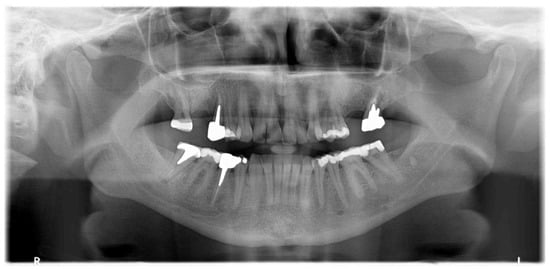

Implant rehabilitation was suggested. For this, a panoramic X-ray was performed, and it showed a homogeneous radiopacity in the left upper jaw, with feathered edges of about 10 mm in dimension (Figure 2).

Figure 2.

Orthopanoramic X-ray showing radiopacity in left upper jaw.

The patient was sent to the oral surgery specialist, who recommended the second-level X-ray examination (CBCT) due to the diagnostic doubt in the panoramic X-ray, thus involving a third specialist, the radiologist. The 3D exam was performed by an oral and maxillofacial center with a cone beam CT scanner with low-dose ionizing radiation, isotropic volume, and a 12 cm field. Axial, panoramic, and cross-section images (dental scan modality) were obtained by multiplanar reconstruction. Image dimensions were real to give the possibility of thickness and distance measurement. A three-dimensional X-ray showed a bone island of juxtacortical hyperdensity and defined edges in the premolar region of the left maxilla (Figure 3).

The final diagnosis of idiopathic osteosclerosis was confirmed. A six-month follow-up showed good healing, and prosthesis on dental implants was performed (Figure 8, Figure 9 and Figure 10).

Figure 9.

Juxta-gingival view of the surgical site: (a) preoperative view; (b) implants’ placement; (c) prosthetic on implants.

Figure 10.

Crowns on implants.